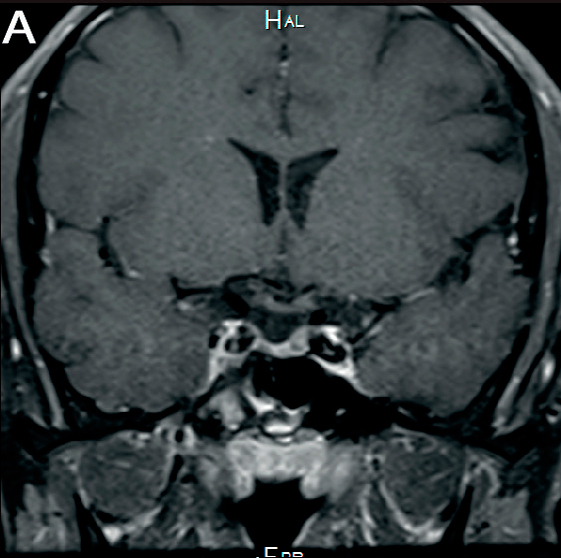

En la evolución se realiza RNM de control 2 años posteriores a primera RMN, que evidencia disminución del tamaño de la lesión tanto en el tallo hipofisario como de la hipófisis (Figura 2).

En lo endocrinológico, la afectación de la glándula hipófiisis se reporta en 5-50% de los pacientes con HCL, lo mas frecuente la deficiencia de arginina vasopresina en 50% de los casos7. Una minoría (5-20%) también presenta disfunción de hormonas de la adenohipófisis4,8,9. En la resonancia magnética nuclear (RMN) se puede encontrar a nivel de sistema nervioso central las siguientes manifestaciones: pérdida del punto brillante de la glándula pituitaria, engrosamiento del tallo pituitario >3 mm con realce, lesión masiva con isointensidad y realce homogéneo bajo imágenes potenciadas en T16.